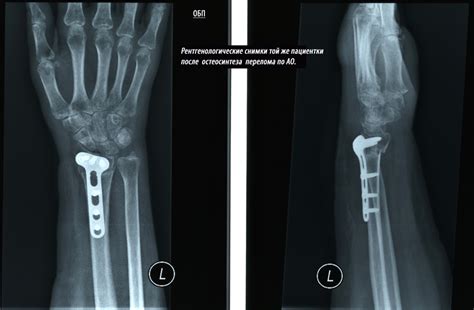

Техника операции остеосинтеза пластиной при дис...